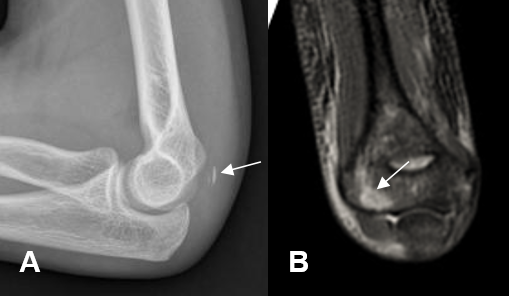

Fig 43 A. Ruptura parcial triceps.

A: Rx lateral. Edema de tejidos blandos y fragmento oseo posterior, por avulsión.

B: RM coronal en STIR. Edema de la microtrabécula, sobre el epicóndilo lateral.

Fig 43 B. Ruptura parcial triceps.

A: RM axial en STIR y B: RM sagital en STIR. Solución de continuidad en algunas fibras del tendón del tríceps, por ruptura parcial.